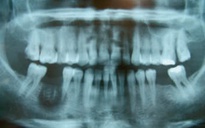

Trong nha khoa hiện đại, thuốc diệt tủy chứa arsenic hầu như không còn được sử dụng mà thay bằng các phương pháp gây tê lấy tủy sống

ẢNH MINH HỌA: AI